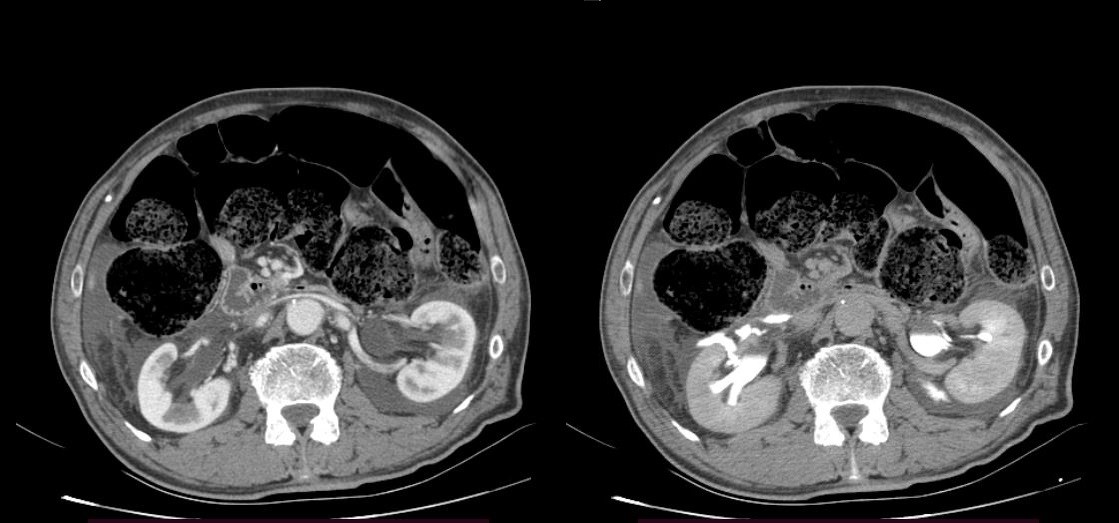

Figure 3.

Figure 2 and 3. As seen on the scans to the left, the surrounding free fluid dif. dx can mean urine, blood. On the scans to the right, the contrast media leakage is evident in the surrounding tissue, meaning there are lesions in the renal pelvis bilaterally.